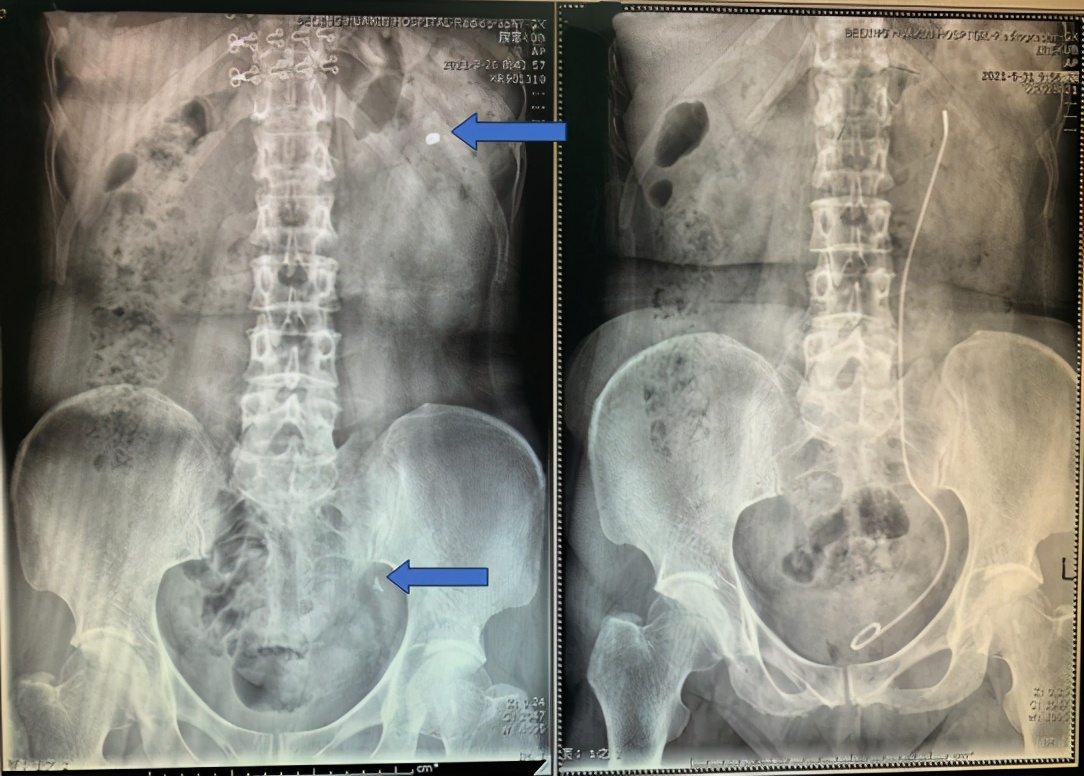

箭头所指为左输尿管结石和左肾结石(左图),术后结石消失(右图)

今年3月份的某个深夜,76岁的赵阿姨因左腰痛伴发热来到第一附属医院急诊科。赵阿姨平时患有高血压、糖尿病及冠心病,入院前3天出现左腰部胀痛,并逐渐出现发热,体温最高38.5℃。于我院做完检查后,结果显示赵阿姨血白细胞及感染指标明显升高,腹平片及泌尿系CT提示左输尿管下段结石、左肾结石合并左肾积水。前来会诊的泌尿外科主治医生王文佳建议赵阿姨立即住院抗感染治疗,并紧急行左输尿管支架置入术以解除结石梗阻。陪同的家属表示不理解,拒绝住院,认为小小的结石不用手术,保守治疗就可以。结果,赵阿姨情况急剧恶化,很快出现高热、寒战,血压下降到70/40mmHg,并伴有胸闷喘憋症状。经ICU大夫会诊后诊断为尿源性脓毒性休克伴心力衰竭,随即转入ICU进行生命支持治疗。在ICU病房经过2天的精心治疗,赵阿姨各项生命体征有所好转。随后,泌尿外科为患者紧急实施左输尿管支架置入术,术中见左输尿管口脓液喷出,术后在泌尿外科继续抗感染治疗2周,患者最终好转出院。

1个月后,赵阿姨感染被完全控制,身体也恢复正常,再次入住泌尿外科,接受左肾结石、左输尿管结石输尿管软镜激光碎石取石术。术中粉末化击碎结石,将肾及输尿管内结石一并击碎取出,术后行结石成分分析显示为磷酸铵镁结石。